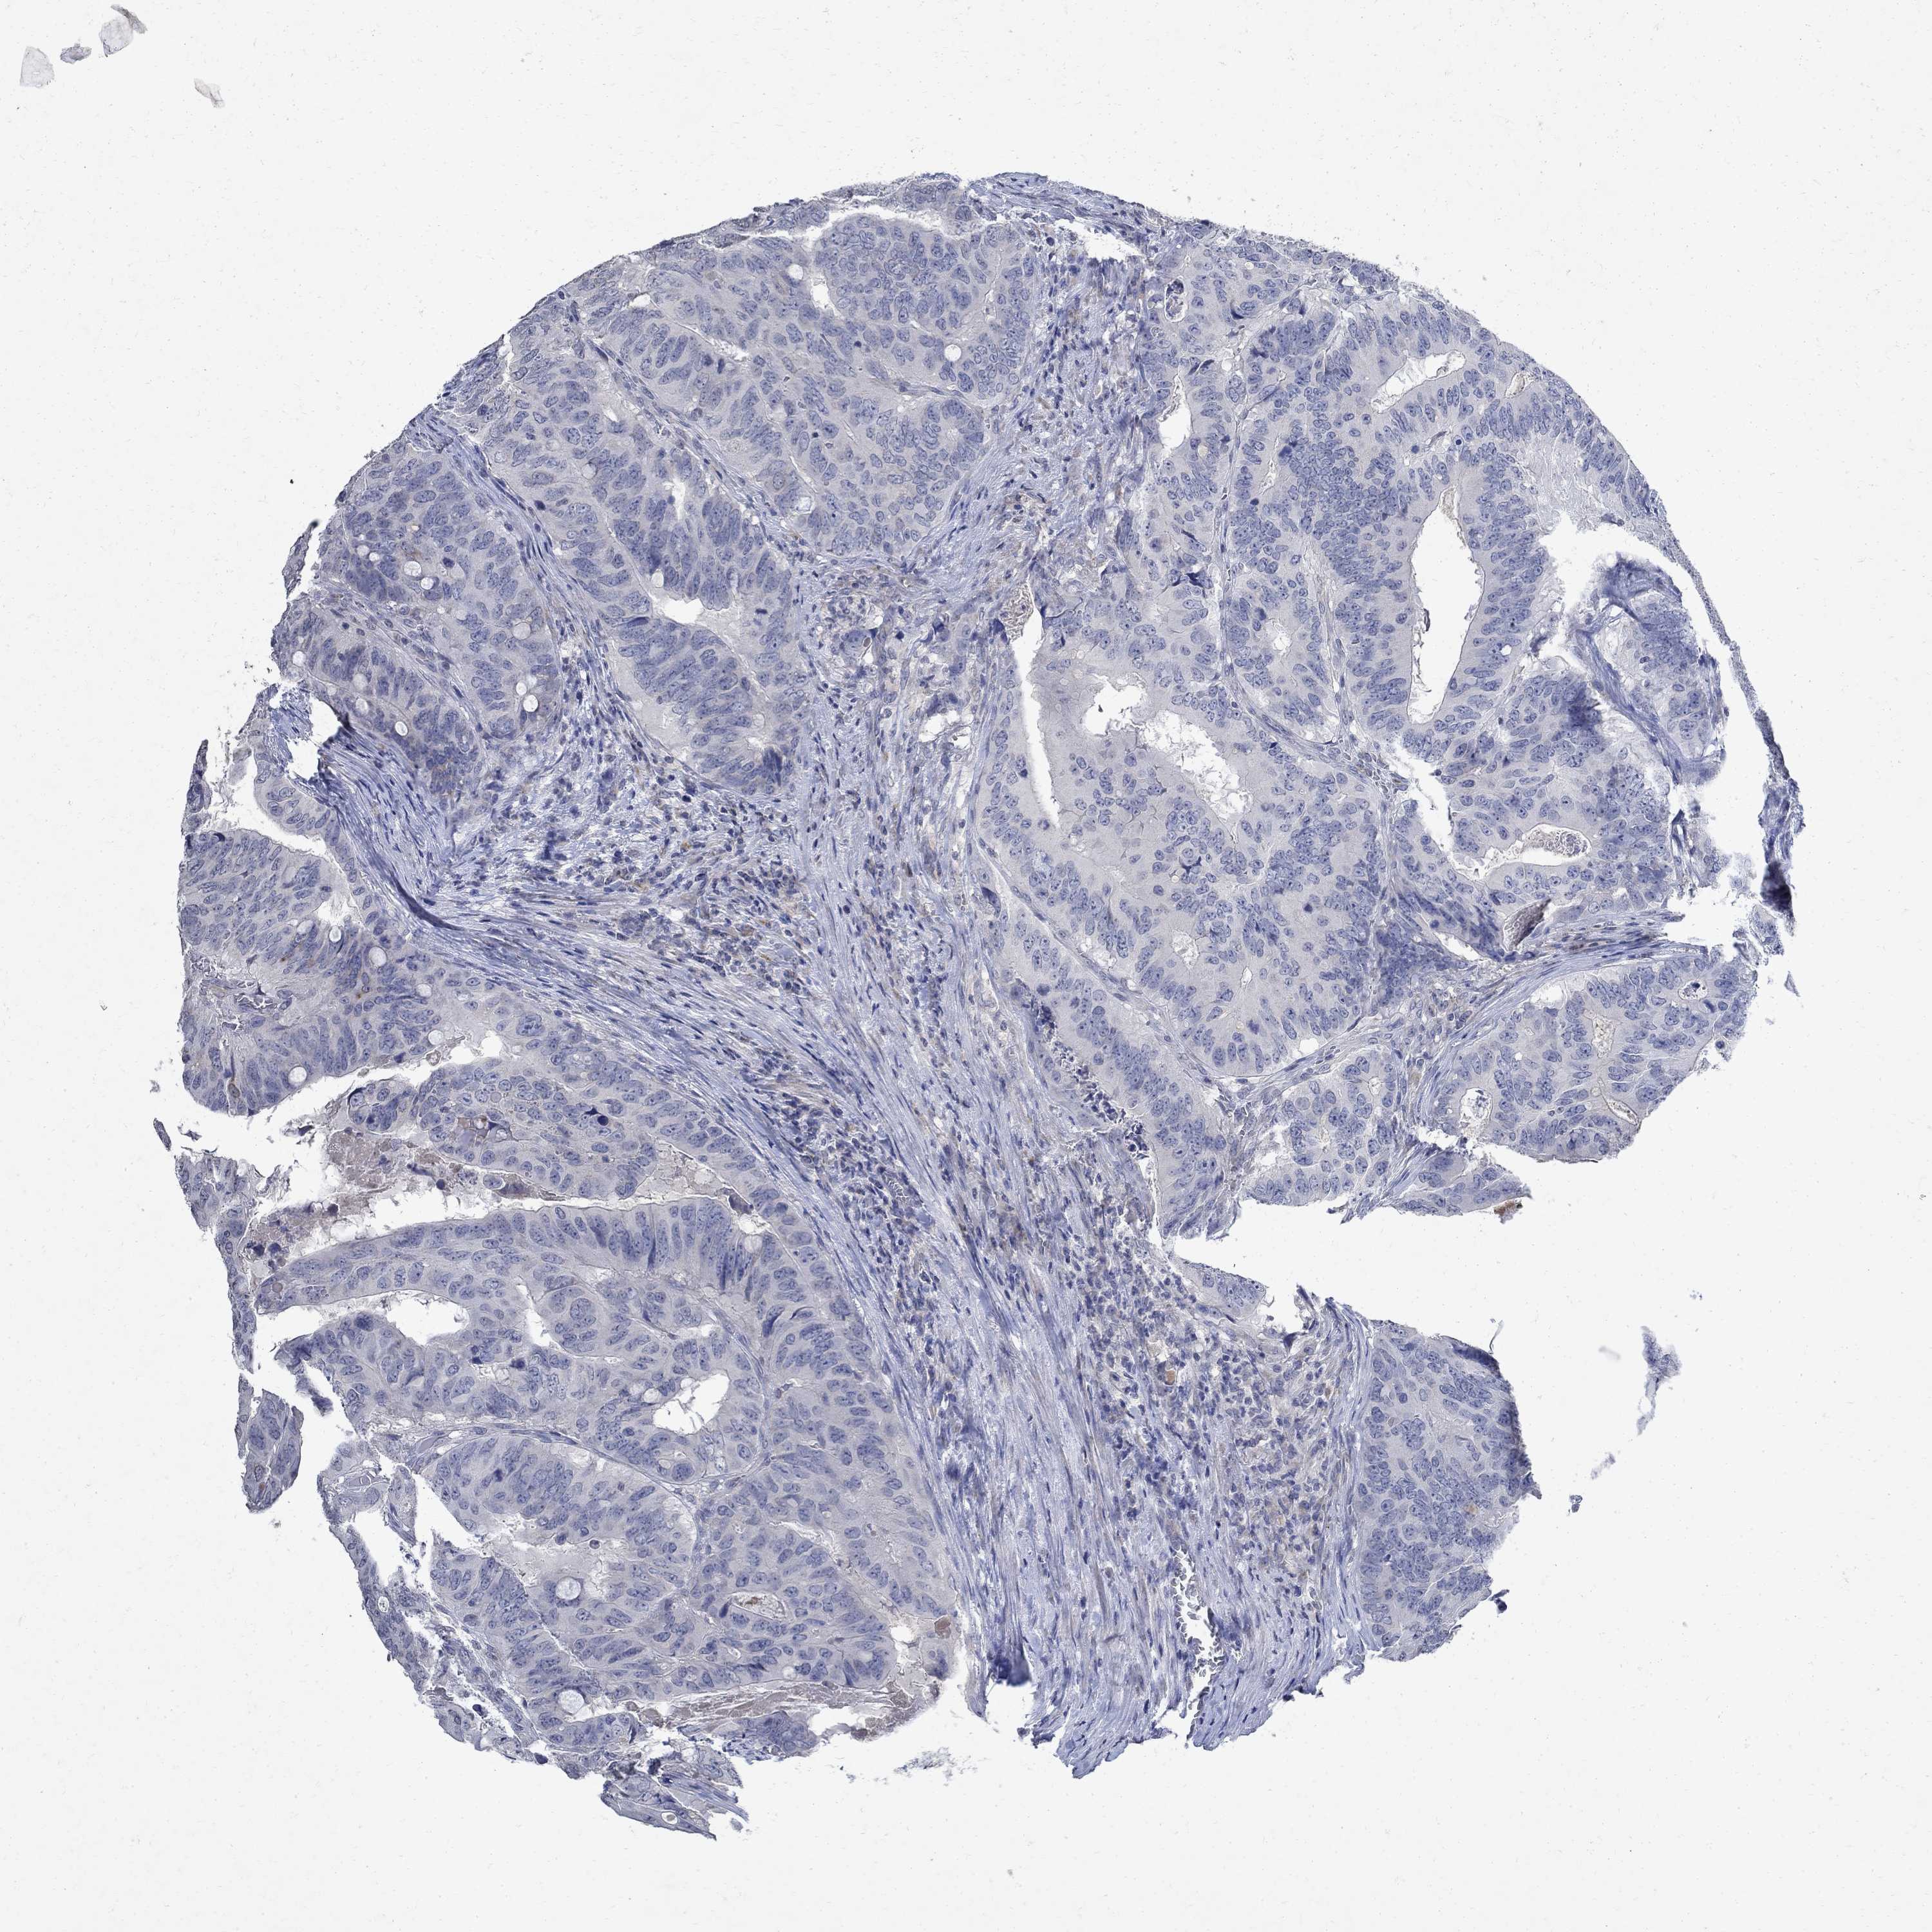

CANCER COLORECTAL CANCER Show tissue menu

Colorectal cancer

Colon adenocarcinoma